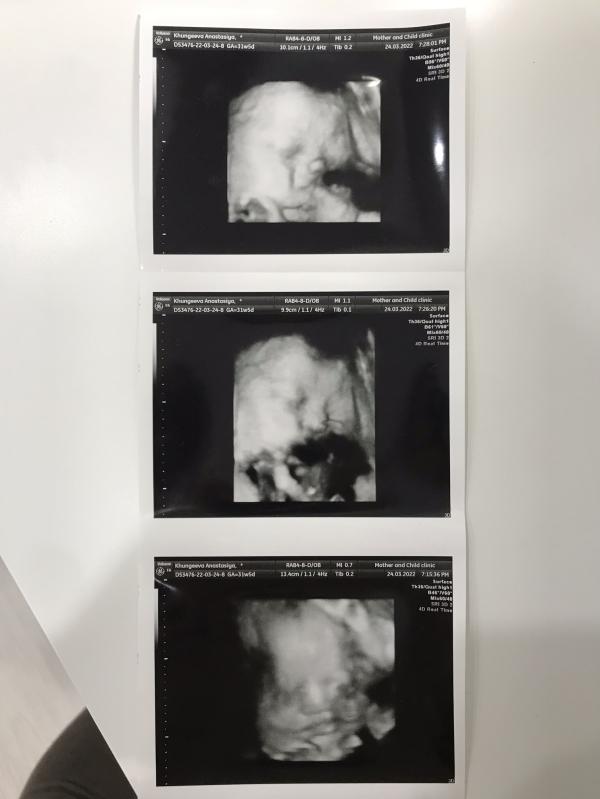

3 УЗИ: Наша стеснительная малышка уже головкой вниз, все в норме, вес 1779 грамм! Ждем!

Сходили сегодня с мужем на 3 УЗИ 🥰 поглядели на нашу стеснительную малышку, которая всё время закрывала лицо ручками и не давала сделать нормально фотографии😁 но в общем, там сидит девчонка, похожая на своих старших брата и сестру😅

Положение у неё уже правильное, головкой вниз) по узи всё в норме👌🏼🙏🏼 кровотоки, плацента, воды - всё ок ☺️

Примерный вес насчитали 1779 грамм😀 старшему в 32 недели ставили 2145 гр, родился в срок 3420 гр) посмотрим, как будет в этот раз 🙂 но в целом там сидит аккуратная такая девчушечка 😍